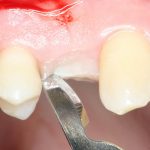

Разрез и скелетирование альвеолярного гребня.

Разрез и скелетирование делаются, исходя из двух взаимоисключающих нюансов: с одной стороны, разрез должен быть минимально травматичным, с другой — обеспечивать хороший обзор:

Мы немного смещаем разрез в сторону нёба для того, чтобы потом нормально сформировать десну. Это видно на правой фотографии выше.